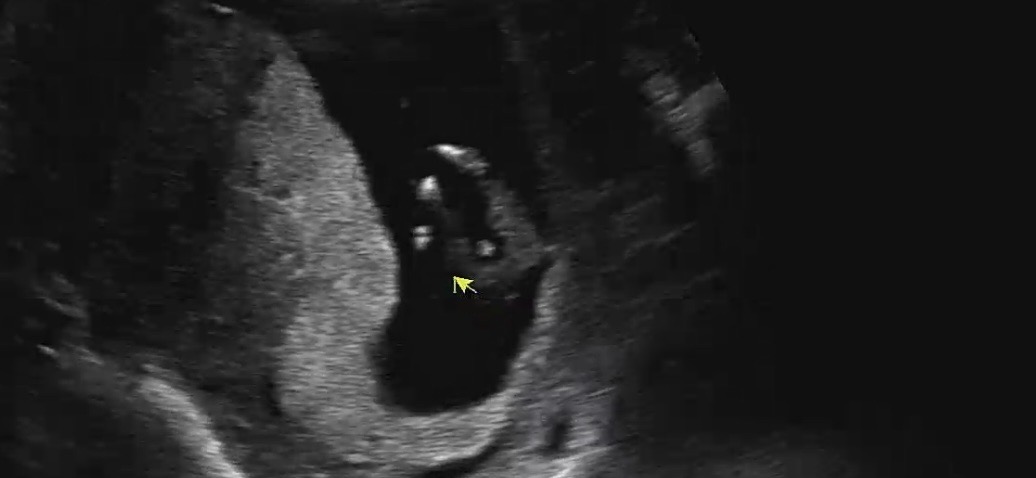

혹시 🌶️인가용????

각도법을 봐도 모르겠어서 올려요! 밑으로 찍은건데 혹시 다리사이에 보이는게 아들인가요??👼